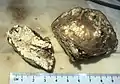

Gout in the joint of the big toe Gross pathology of a large tophus

Gross pathology of a large tophus